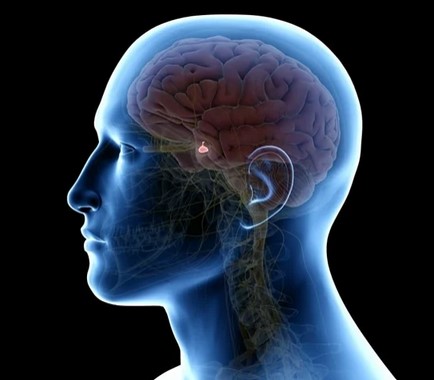

Growth hormone (GH) is a substance in the body that helps kids grow and develop. It Is produced by our brain’s pituitary gland and governs our height, bone length and muscle growth

Where is the pituitary gland?

A small gland between the lobes of the brain